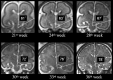

Fig 3.

Coronal T2-weighted single-shot, fast spin-echo sections depicting the change of HIA value in 6 representative cases of different GA.